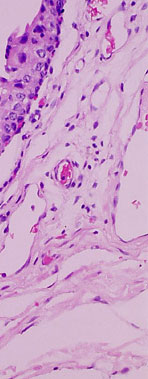

However, at higher magnification, there is evidence of intraepithelial microcyst formation which is not a post mortem artifact. The microcysts contain pale pink mucoproteins. There is also mild patchy hyperplasia of the mucosa.